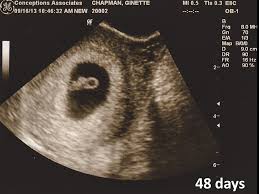

So what does baby look like at 7 weeks pregnant. At 7 weeks pregnant your baby is the size of a blueberry. Now you can figure out your due date and use an ultrasound to detect the baby s heartbeat and brain development. Baby at 7 weeks.

This is the stage where the fetus looks more like a tadpole and less like a baby and measures only about an inch 2 5 centimeters. On the other hand as part of the ongoing baby development at 7 weeks pregnant the arm buds of the baby will start to form and grow along with the leg buds which will begin to resemble tiny paddle by the end of week 7 of the pregnancy. The eyes of the baby at 7 weeks pregnant will be wide open but they will not have any irises as yet. Morning sickness swollen breasts and food aversions are some common symptoms at 7 weeks.